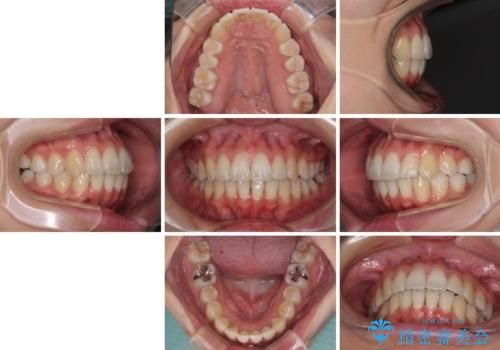

骨格的な問題を抱えた左奥以外は比較的早く咬み合わせが改善しましたが、左奥はどこで咬み合えば良いのか分からず、大変不便な思いをされていました。

ゴムかけにご協力いただき、最終的には反対咬合を改善することができ、患者様には大変満足していただきました。